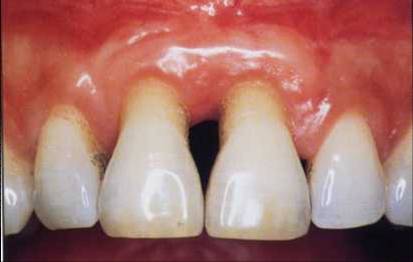

Klinisch ist eine Gingivitis daran zu erkennen, dass das Zahnfleisch etwas röter wird und seine Stippelung verloren geht. Bereits bei leichter Berührung beginnt es zu bluten. Eine Parodontitis erkennt man im Rahmen der zahnärztlichen Untersuchung, indem man die Tiefe der Zahnfleischtaschen sondiert (sie sind tiefer als normal) und eine Röntgenaufnahme des Kieferknochens macht (die Knochengrenze ist verschoben, siehe Abbildung 7). Ohne zahnärztliche Untersuchung macht sich eine Parodontitis am ehesten durch die länger erscheinenden Zähne und das Fehlen der Zahnpapillen bemerkbar (Abbildung 8). Beides entsteht dadurch, dass das Zahnfleisch dem Knochen folgt. Aber auch starker Mundgeruch ist häufig ein Zeichen für eine Parodontitis.